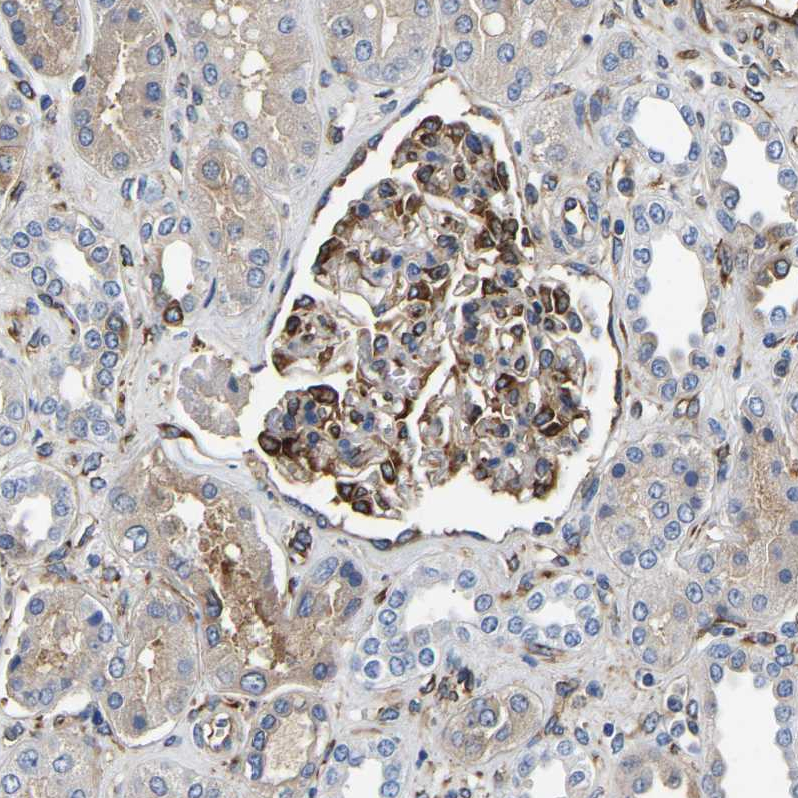

Immunohistochemical staining of human cerebral cortex shows strong cytoplasmic positivity in endothelial cells and glial cells.